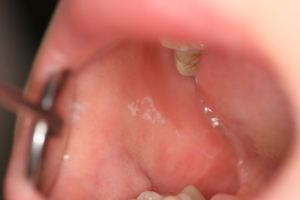

症例です

頬粘膜に白い病変を認めます。

(写真が上下逆になっています)

鑑別疾患に扁平苔癬などがありますが、

カンジダ症ではガーゼなどで拭うことができます。